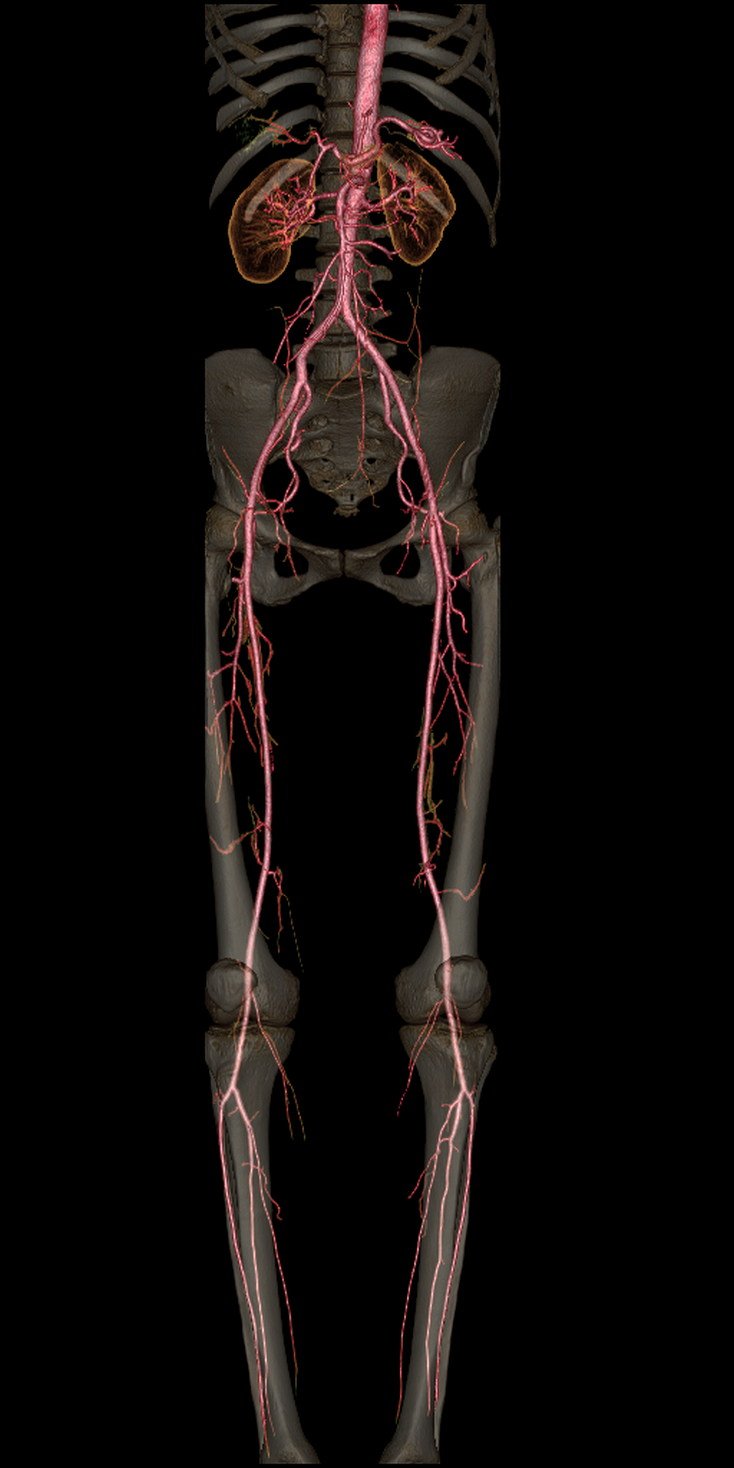

Lower Limb Angiography